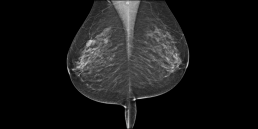

57 year-old woman, without risk factors, comes for a screening mammogram.

A 17mm mass (spicules included), not visible on the previous shot, is discovered in mammography, this mass is classified BI-RADS 5. MammoScreen® points this mass with a score of 8, as well as a second known benign mass. The mass measures 12 mm in ultrasound. The biopsy confirms CNST grade 1 Luminal A RO+ RP- HER2 low, Ki67 3%.